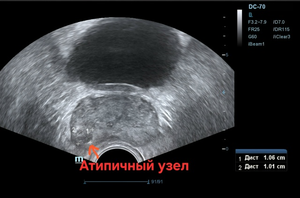

Всё бы ничего, но только на ТРУЗИ объём простаты несколько превышен — 39,6см³, а в периферической зоне справа округлый т. н. атипичный узел диаметром 11,0 мм со слабым кровотоком (фото 1 — 3); а по статистике именно в этой зоне выявляется до 70% рака.

Фото 2 — ТРУЗИ, атипичный узел